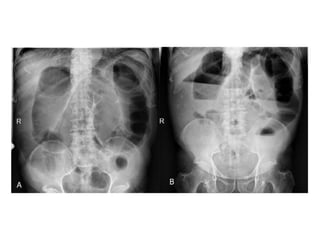

• La triada clásica de

obstrucción en el examen

radiológico es:

o Asas de intestino delgado dilatadas

(mayores a 3 cm)

o Niveles hidroaéreos

o Ausencia de aire distal

El diagnóstico seconfirm a mediante estudios radiológicos SERIE ABDOMINAL Rx abdomen paciente en posición supina Rx tórax Rx abdomen con enfermo de pie SENSIBILIDAD DEL 70 AL 80%

• La triadaclásica de obstrucción en el examen radiológico es: o Asas de intestino delgado dilatadas (mayores a 3 cm) o Niveles hidroaéreos o Ausencia de aire distal